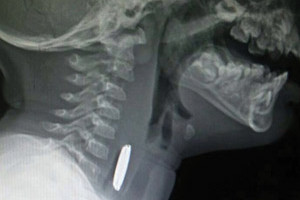

أخصائي طب الأسنان: التهاب اللثة أثناء الحمل يؤثر على صحة الجنين